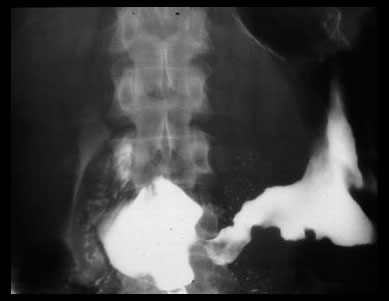

NEPHROCALCINOSIS

There are multiple calcifications of the kidneys (nephrocalcinosis) as a result of hypercalcemia. Note enlarged retroperitoneal lymph nodes (arrows) which is a common finding in sarcoidosis.